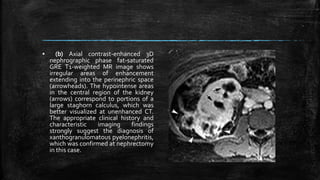

▪ Xanthogranulomatous

pyelonephritis in a 32-year-old

woman with diabetes

and Proteus infection of the

urinary tract. (a) Coronal

steady-state fast spin-echo T2-

weighted MR image shows a

poorly defined mass

(arrowheads) in the lower pole

of the right kidney and

hydronephrosis (arrows) in the

upper pole.

▪ (b) Axial contrast-enhanced 3D

nephrographic phase fat-saturated

GRE T1-weighted MR image shows

irregular areas of enhancement

extending into the perinephric space

(arrowheads). The hypointense areas

in the central region of the kidney

(arrows) correspond to portions of a

large staghorn calculus, which was

better visualized at unenhanced CT.

The appropriate clinical history and

characteristic imaging findings

strongly suggest the diagnosis of

xanthogranulomatous pyelonephritis,

which was confirmed at nephrectomy

in this case.